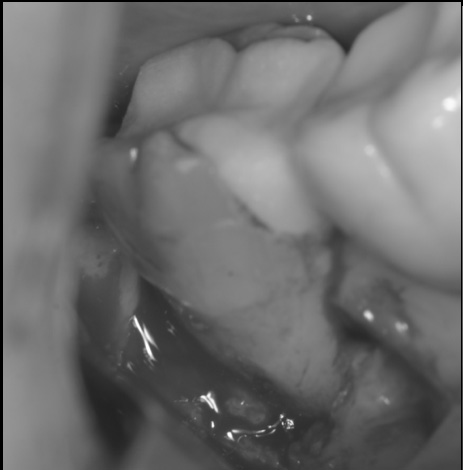

フラップを起こすと不良肉芽と根面に歯石を認めた。